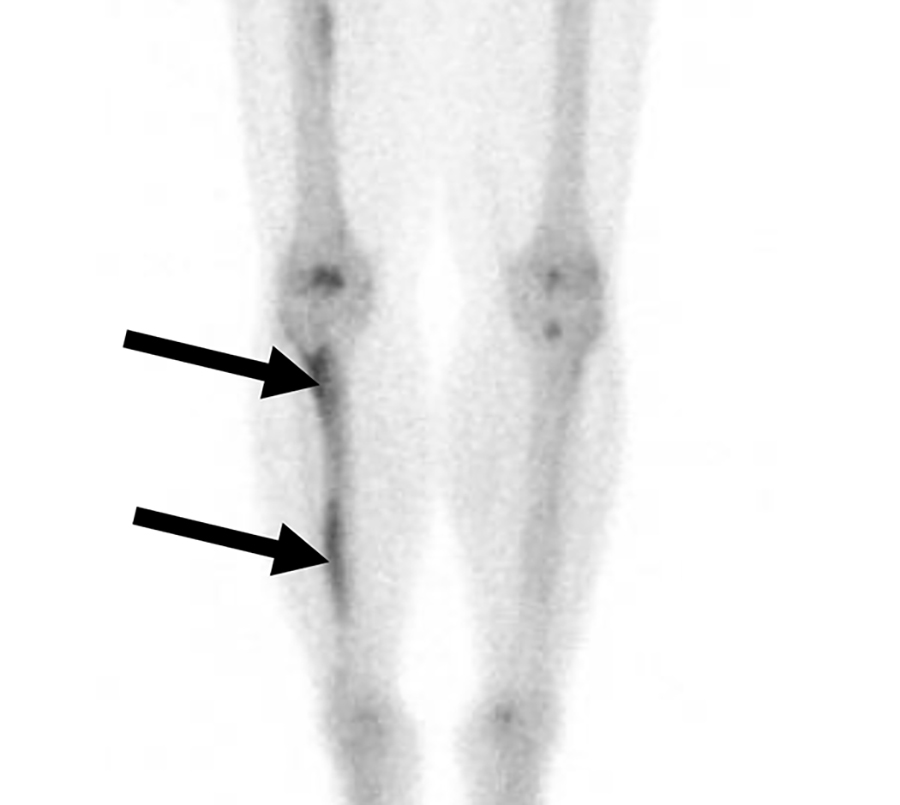

Malattia di Erdheim-Chester in un uomo di 47 anni con dolore osseo aspecifico.

La scintigrafia ossea whole-body evidenzia un’intensa ipercaptazione simmetrica e confluente a carico delle ossa lunghe (in particolare distretto dia-metafisario ed epifisario di ginocchia e caviglie). Come reperto incidentale, si osserva un ristagno di tracciante nel rene destro, indice di ostruzione delle vie urinarie.

La TC conferma una marcata osteosclerosi nelle medesime sedi ipercaptanti e la presenza di una massa tissutale infiltrante che avvolge simmetricamente i reni (aspetto a “cercine” o hairy kidney) e infiltra il mesentere. Questa fibrosi retroperitoneale spiega l’ostruzione dell’efflusso renale destro rilevata in scintigrafia.

La malattia di Erdheim-Chester è una rara istiocitosi non-Langerhans caratterizzata da una proliferazione sistemica di macrofagi. Il pattern di osteosclerosi simmetrica dia-metafisaria bilaterale delle ossa lunghe, associato all’infiltrazione perirenale, è considerato un quadro radiologico quasi patognomonico per questa patologia.